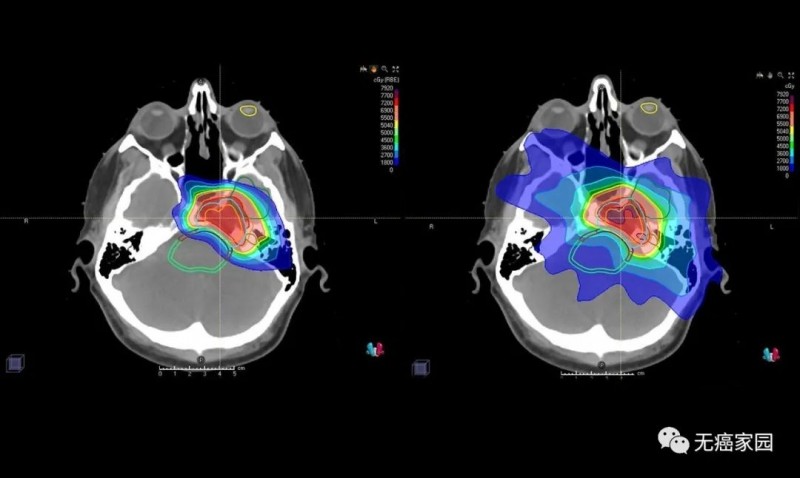

图中患者的脑部扫描显示质子(左)如何专门针对肿瘤,而对周围组织和结构的辐射最小,传统的光子辐射(右)会损坏周围的组织和结构